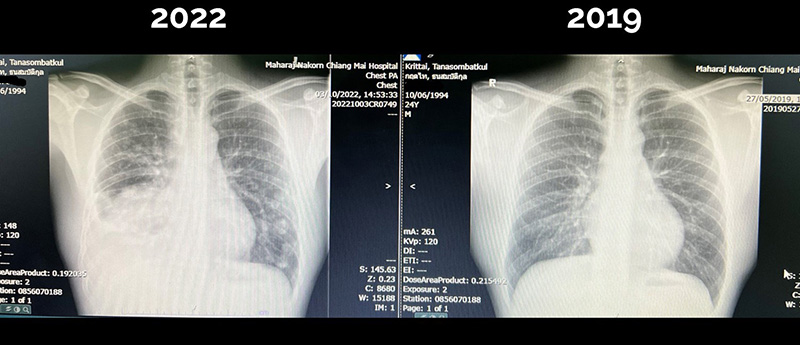

หมอกฤตไท อัปเดตอาการหลังป่วยเป็นมะเร็งปอดในอายุ 28 ปี เข้ารับเคมีบำบัดครั้งที่ 3 ผลข้างเคียงผมร่วง แต่ผลเอกซเรย์ปอดดีขึ้น ก้อนใหญ่ด้านขวาเล็กลง ก้อนเล็กปอดซ้ายจางลง

ซึ่งปัจจุบันเอกซเรย์ปอดดูดีขึ้นครับ ก้อนใหญ่ด้านขวามีขนาดเล็กลง และก้อนน้อย ๆ ที่ปอดซ้ายก็ดูจางลงครับ ผลข้างเคียงที่ชัด ๆ ก็มีแค่เรื่องผมร่วง กับอ่อนเพลีย ยังไม่มีผลข้างเคียงรุนแรงอะไร